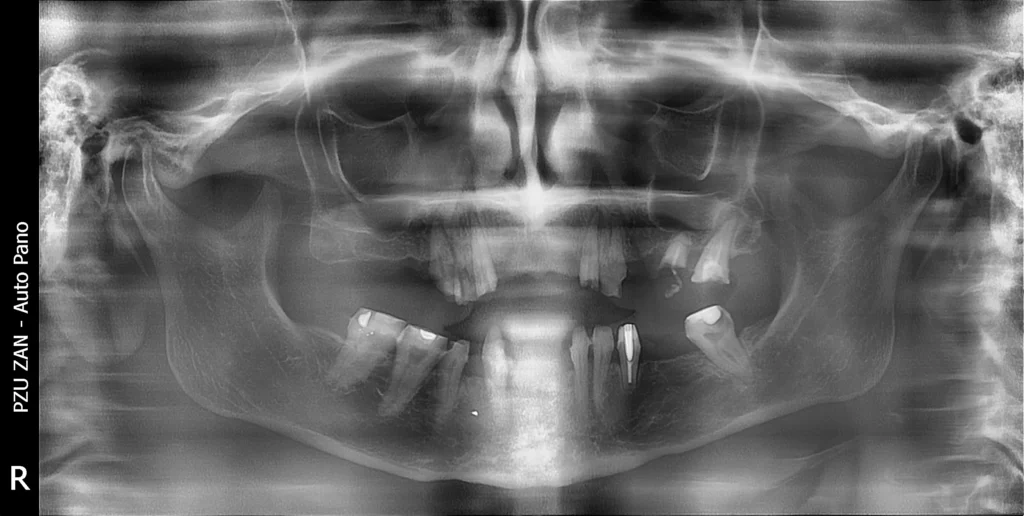

After a careful examination and analysis the plan was to extract all her teeth in the upper jaw and keep some in the lower jaw for easier transition for the patient.

Immediately after the extraction 6 implants were placed in the upper jaw and 5 dental implants in the lower jaw. The implant therapy was executed with a digital workflow and using surgical guides. She was provided with fixed temporary teeth for the healing period.

After 6 months of healing and osseointegration of the dental implants, the patient came back for her final restoration. The case was a difficult Class III with advancement of the lower jaw.